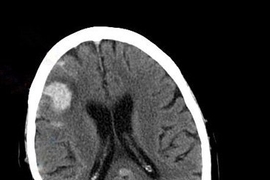

MIT and Boston Children’s Hospital researchers have devised a minimally invasive way to monitor intracranial pressure in patients suffering from traumatic brain injuries or infectious diseases. Current techniques for measuring pressure within the brain are so invasive that the measurement is only performed in high-risk patients.

Traumatic brain injuries, as well as infectious diseases such as meningitis, can lead to brain swelling and dangerously high pressure in the brain. If untreated, patients are at risk for brain damage, and in some cases elevated pressure can be fatal.

Under normal conditions, ICP is between 5 and 15 millimeters of mercury (mmHg). When the brain suffers a traumatic injury or swelling caused by inflammation, pressure can go above 20 mmHg, impeding blood flow into the brain. This can lead to cell death from lack of oxygen, and in severe cases swelling pushes down on the brainstem — the area that controls breathing — and can cause the patient to lose consciousness or even stop breathing.

Measuring ICP currently requires drilling a hole in the skull and inserting a catheter into the ventricular space, which contains cerebrospinal fluid. This invasive procedure is only done for patients in intensive care units who are at high risk of elevated ICP. When a patient’s brain pressure becomes dangerously high, doctors can help relieve it by draining cerebrospinal fluid through a catheter inserted into the brain. In very severe cases, they remove a piece of the skull so the brain has more room to expand, then replace it once the swelling goes down.